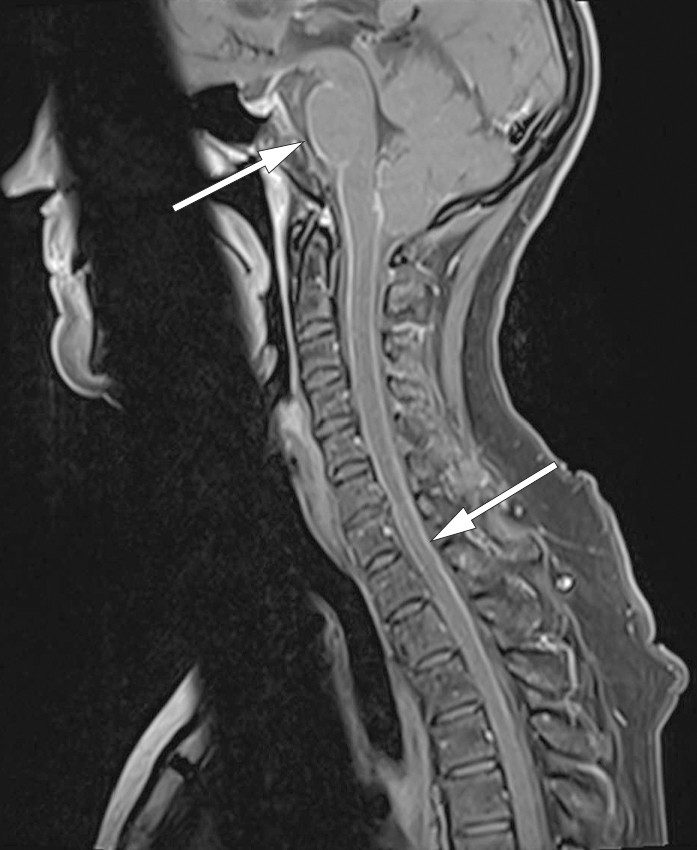

Man gjorde derfor kontrastforsterket MR-undersøkelse av medulla, som viste nytilkomne intramedullære forandringer forenlige med myelitt og meningitt (figur 2 og 3). På dette tidspunktet hadde det tilkommet diskrete trunkale sensoriske forstyrrelser og lett hyperrefleksi i underekstremitetene.